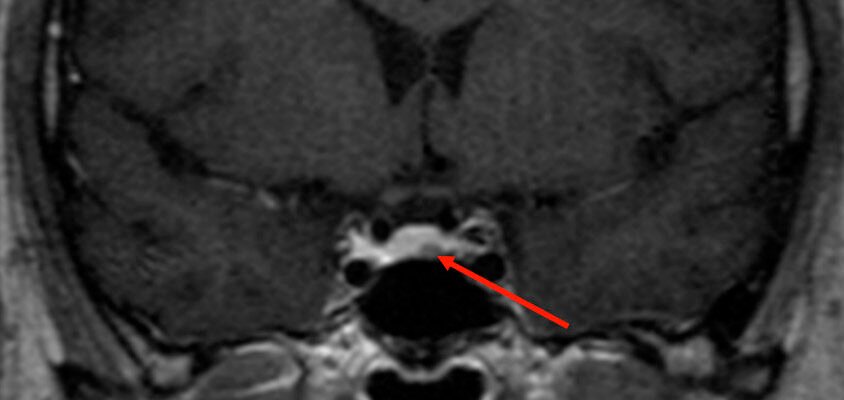

Гіпофіз — крихітна, але могутня залоза, що регулює чимало важливих функцій в організмі. І коли в цій залозі починається рости мікроаденома, все змінюється. Вона може впливати на вироблення гормонів, і то суттєво. А симптоми можуть бути різними, від головного болю до змін у рівні гормонів, і навіть впливати на зір. Як таке можливе? Це досить просто: гіпофіз розташований під мозком у маленькому заглибині – турецькому сідлі. І будь-яке новоутворення тут може стискати довколишні структури мозку.